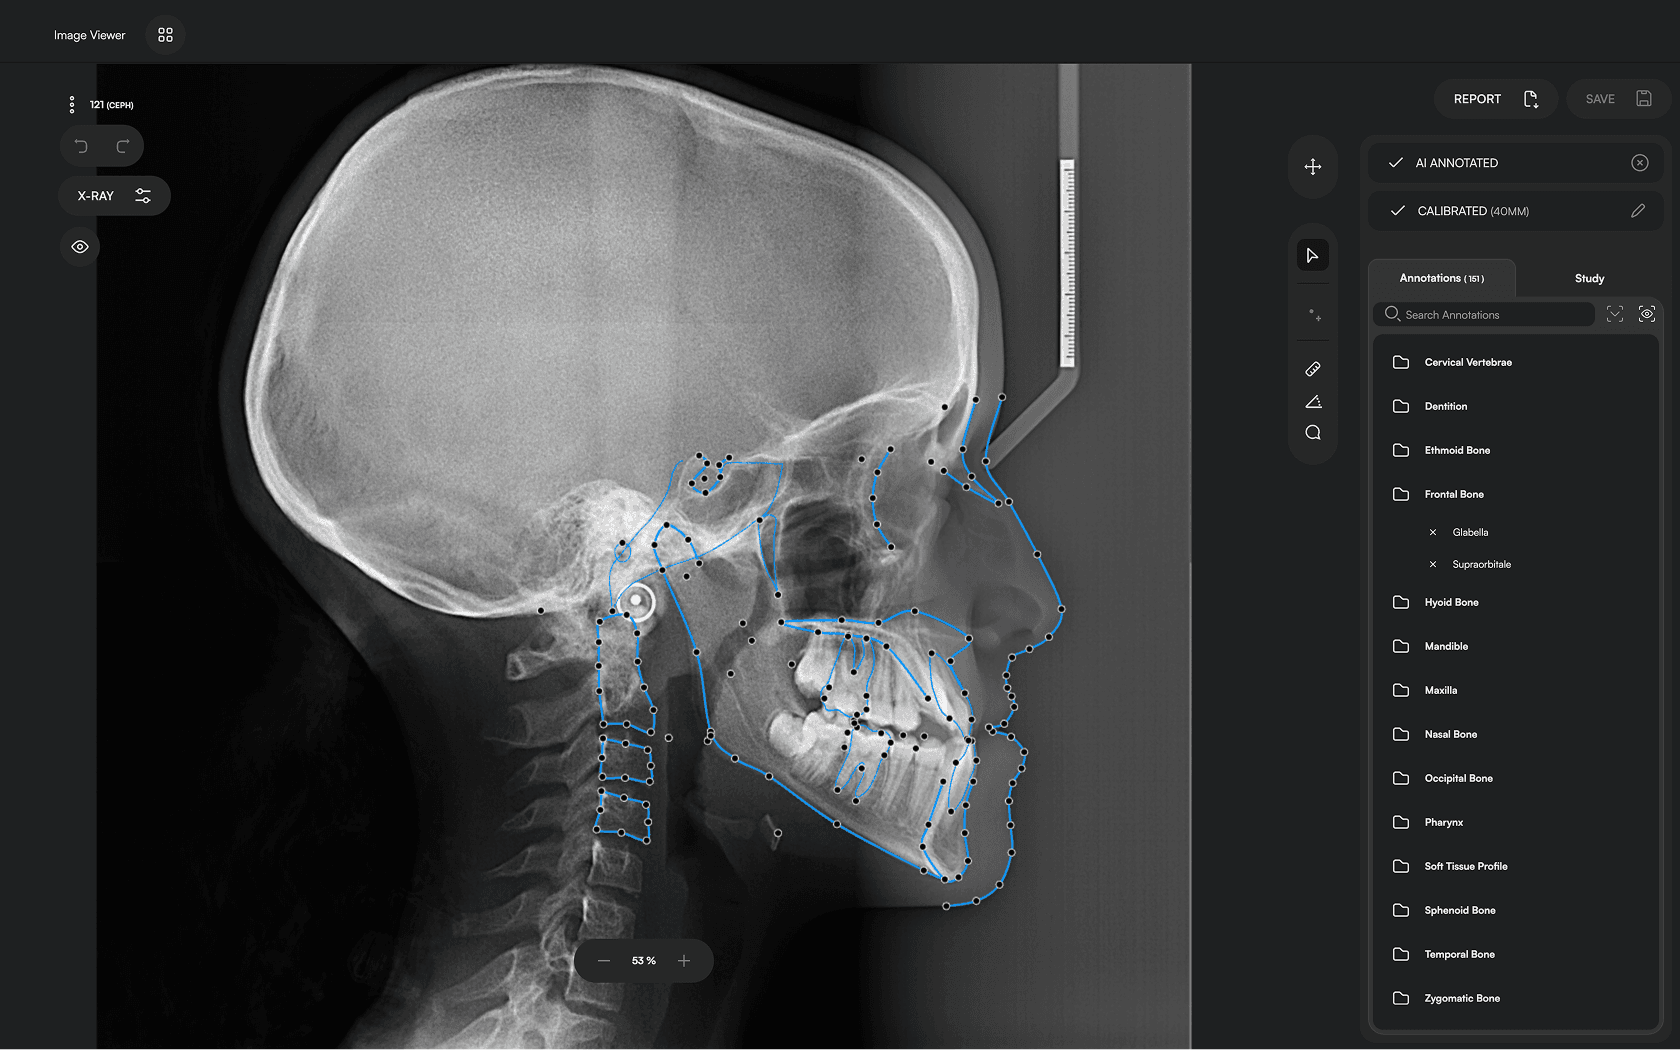

150+ landmarks traced in seconds

Diverse Analysis

Access automated studies like Steiner and Jefferson to assist in clinical assessment and enhance case evaluations.

Powerful Insights

Experience a comprehensive assessment of skeletal, dental, and soft tissue discrepancies.